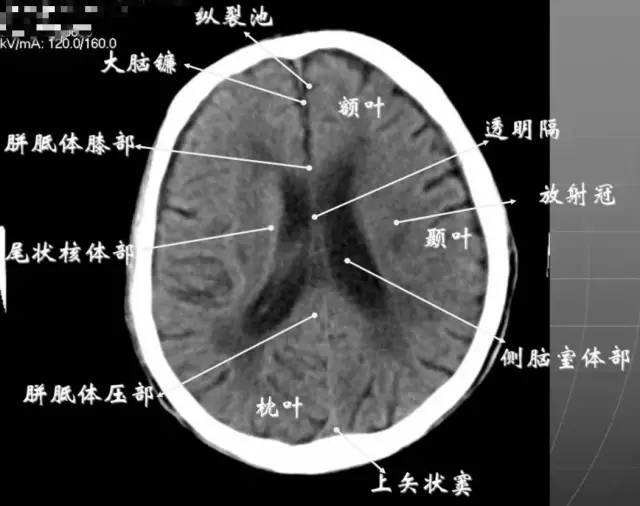

5、侧脑室体部层面

由额、颞、枕叶构成,两侧侧脑室体部之间为透明隔,外侧为尾状核和体部。侧脑室后角(枕角)可不对称,室内可见脉络丛钙化。中线处可见大脑纵裂池和大脑镰。

6、侧脑室上部层面内侧壁侧脑室体部被胼胝体分开,侧脑室体部的外方为顶叶,顶枕沟及中央沟将大脑为为额、顶、枕叶。

7、大脑皮质下部层面(半卵圆中心层面)在胼胝体和侧脑室上方,大脑镰自前向后贯穿中线。白质部分为半卵圆中心,额叶范围缩小,顶叶所占比例扩大,枕叶基本消失。

半卵圆中心:位于胼胝体上方,由左右大脑半球髓质形成的有髓纤维,对称位于大脑镰两侧区域。

8、大脑皮质上部层面(半卵圆区上部层面)已近颅顶,大脑镰清晰可见,其旁的脑灰质和脑沟十分清楚。顶叶较小,额叶较小。

放射冠:是内囊到大脑皮质间的放射状纤维白质。